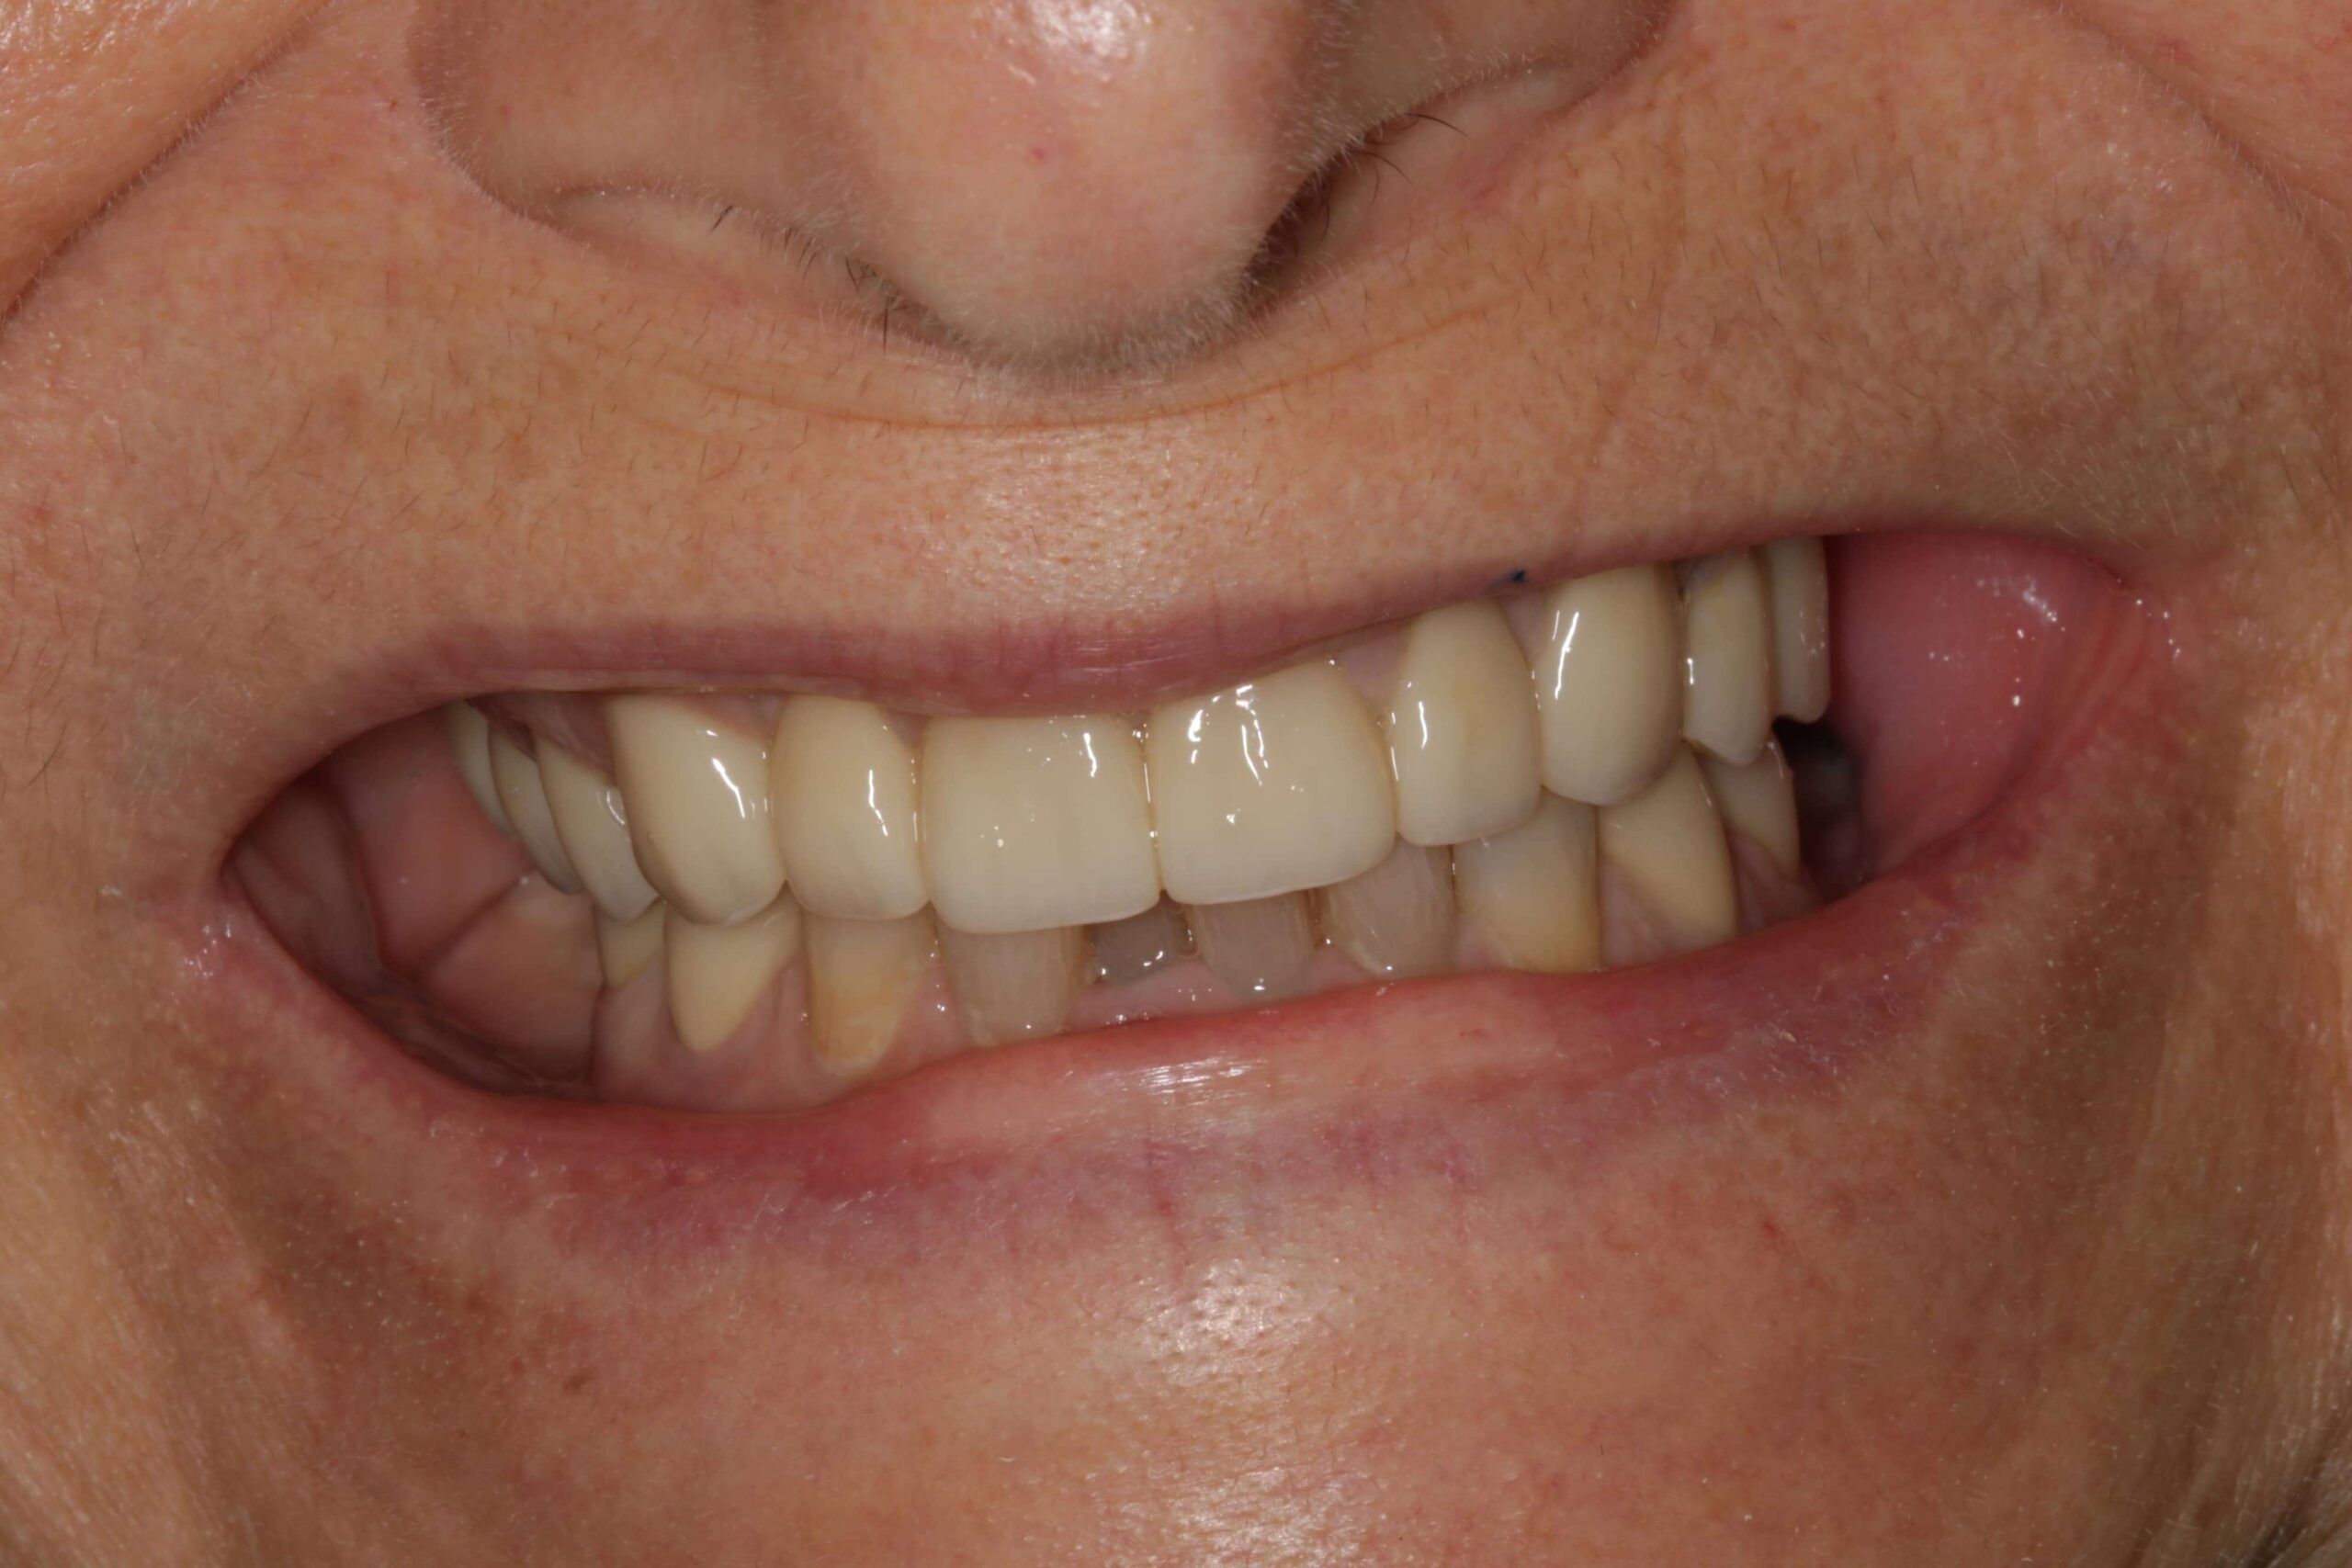

- Nem megfelelően kialakított fogpótlások: rosszul illeszkedő koronák, hidak vagy kivehető pótlások hosszú távon megváltoztathatják a harapási viszonyokat, túlterhelhetik az állkapocsízületet, és funkcionális egyensúlyzavart idézhetnek elő. Ez gyakran vezet feszüléshez, rágás közbeni fájdalomhoz vagy ízületi kattogáshoz.

Az állkapocsfájdalom kezelése

Az állkapocsfájdalom kezelése mindig az okok pontos meghatározásán alapul. Egyes esetekben elegendő lehet az otthoni tehermentesítés, máskor fogászati, gnatológiai vagy szájsebészeti beavatkozás válik szükségessé.

Fogászati kezelés

Az állkapocsfájdalom nem csupán kellemetlen tünet, hanem gyakran valamilyen komolyabb állapot figyelmeztető jele. Legyen szó állkapocs ízületi gyulladásról, fogászati problémáról, fertőzésről vagy izomeredetű feszültségről, a panaszokat nem érdemes elhanyagolni. A szakszerű diagnózis és a célzott kezelés – legyen az fogászati beavatkozás, fizioterápia vagy állkapocstorna – jelentősen javíthatja a páciens életminőségét.

Amennyiben fájdalmat, kattogást, feszülést vagy rágási nehézséget tapasztal, érdemes mihamarabb szakértő segítséget kérni. Az Uniklinik Fogászat és Implantációs Központban tapasztalt szakorvosaink komplex szemlélettel – beleértve a gnatológiai diagnosztikát is – állnak rendelkezésére a kiváltó okok feltárásában és a személyre szabott megoldások kidolgozásában.